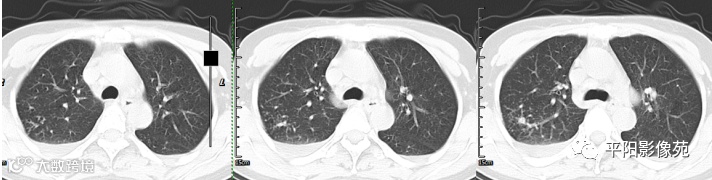

胸部